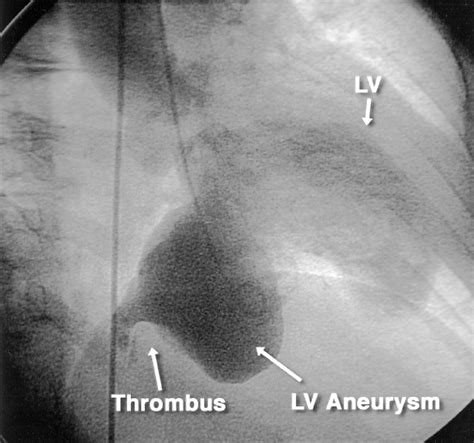

• Cardiac Catheterization: This invasive procedure involves inserting a catheter into the heart to measure pressure and blood flow, and to visualize the coronary arteries.

• Thromboembolism: Blood clots can form in the aneurysm and travel to other parts of the body, causing blockages in blood vessels.